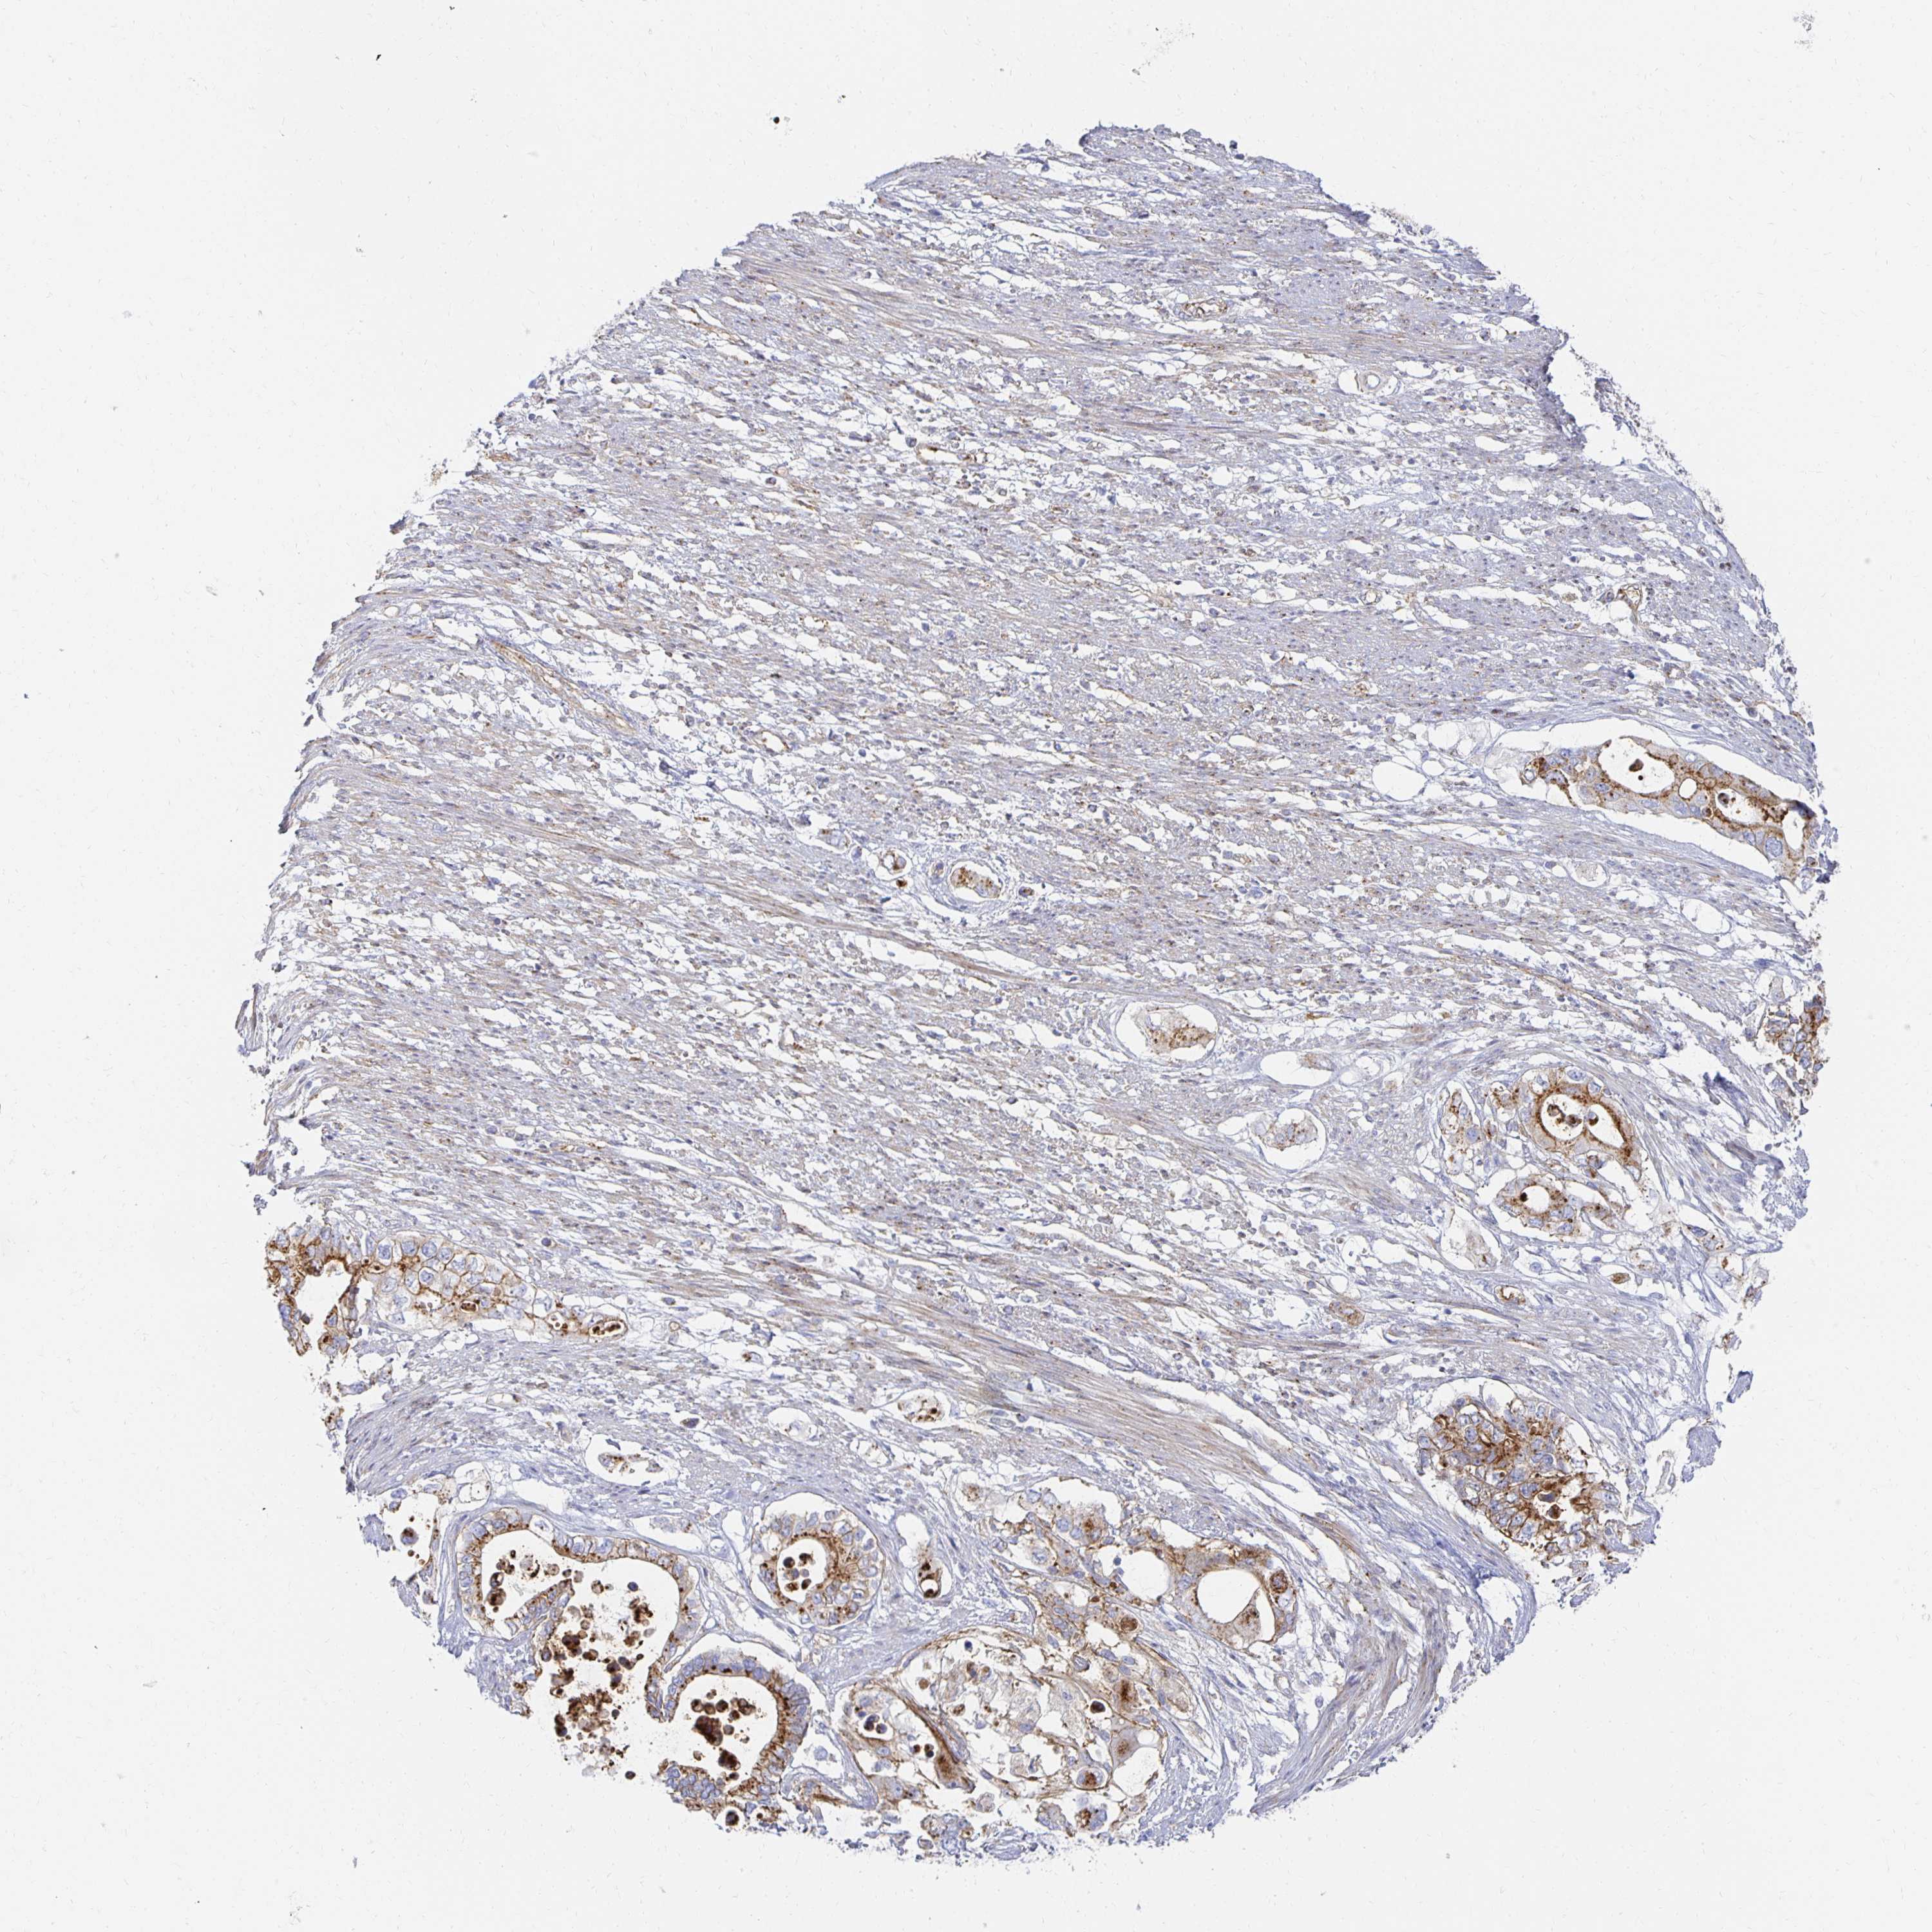

PANCREATIC CANCER - Protein expressioni

A mouse-over function shows sample information and annotation data. Click on an image to view it in a full screen mode. Samples can be filtered based on level of antibody staining by selecting one or several of the following categories: high, medium, low and not detected. The assay and annotation is described here.

Note that samples used for immunohistochemistry by the Human Protein Atlas do not correspond to samples in the TCGA dataset.

Antibody stainingi

Antibody staining in the annotated cell types in the current human tissue is reported as not detected, low, medium, or high, based on conventional immunohistochemistry profiling in selected tissues. This score is based on the combination of the staining intensity and fraction of stained cells.

Each image is clickable and will lead to virtual microscopy that enables deeper exploration of all samples and also displays staining intensity scores, fraction scores and subcellular localization as well as patient and tissue information for each sample.

Antibody HPA055614

Staining

High

Medium

Low

Not detected

Intensity

Strong

Moderate

Weak

Negative

Quantity

>75%

75%-25%

<25%

None

Location

Nuclear

Cytoplasmic/membranous

Cytoplasmic/membranous,nuclear

Adenocarcinoma, NOS